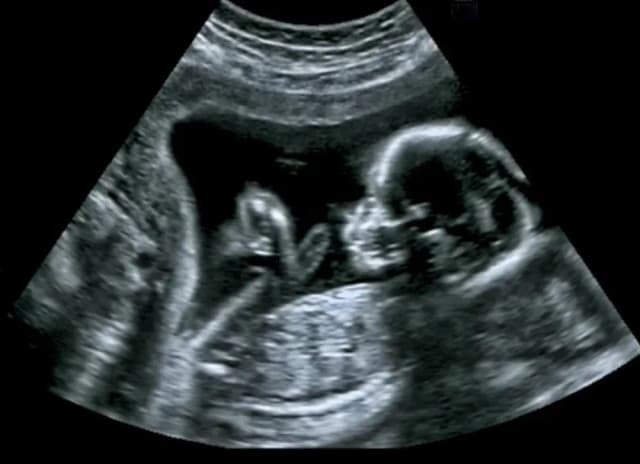

Badania połówkowe na czym polegają? Dowiedz się, jak USG II trymestru ocenia rozwój płodu i zdrowie matki oraz jakie korzyści przynosi.